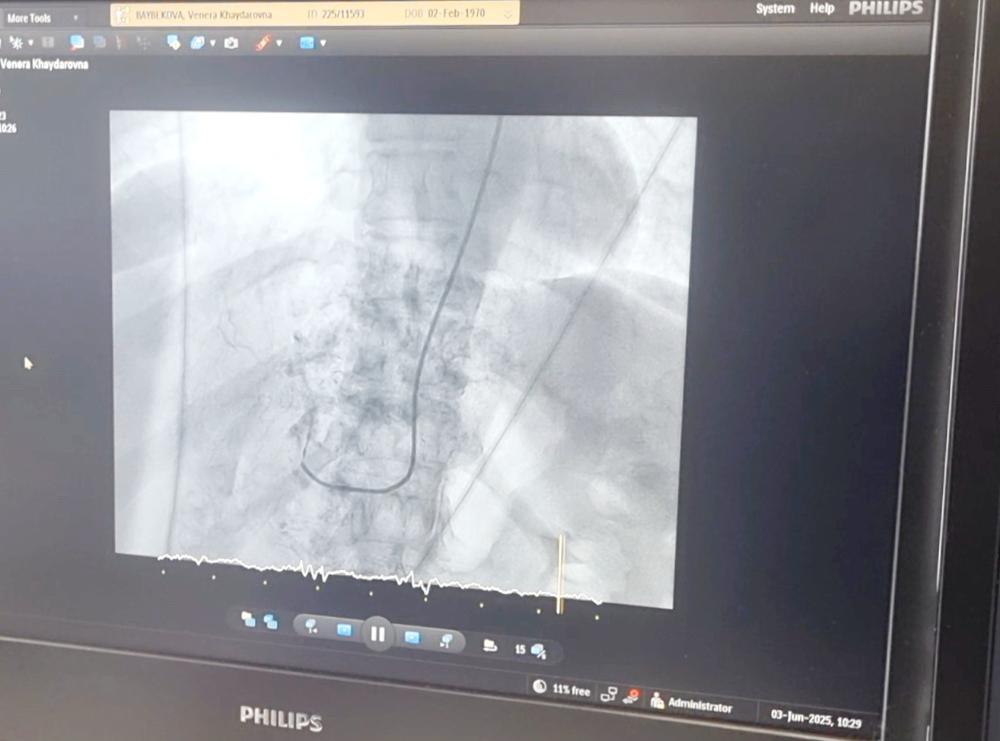

На базе регионального сосудистого центра больницы селективную химиоэмболизацию сосудов изучили пензенские врачи-онкологи и врачи–рентгенохирурги.

Особенностями применения технологии с пензенскими коллегами поделился к.м.н., врач по рентгенэндоваскулярным методам диагностики и лечению, врач-онколог МРНЦ им А.Ф. Цыба - филиала НМИЦ радиологии Минздрава России Фёдор Трифонов.

«Эмболизация – это вид эндоваскулярной хирургии, при котором происходит блокирование сосуда при помощи специального специальных эмболизационных препаратов, - пояснил Фёдор Александрович. - Эмболизация отличается наименьшим риском для пациента и временем восстановления».

В рамках мастер-класса во вторник, 3 июня, в больнице проведены три операции пациентам, у которых имелись образования разных локализаций.

«Под контролем ангиографа при помощи химиопрепарата произведена химиоинфузия, которая позволяет закрыть сосуд, чтобы опухоль перестала питаться, - уточнил главный врач Областного онкологического клинического диспансера, также изучающий данную технологию в рамках мастер-класса. - В результате образование уменьшается в размерах».